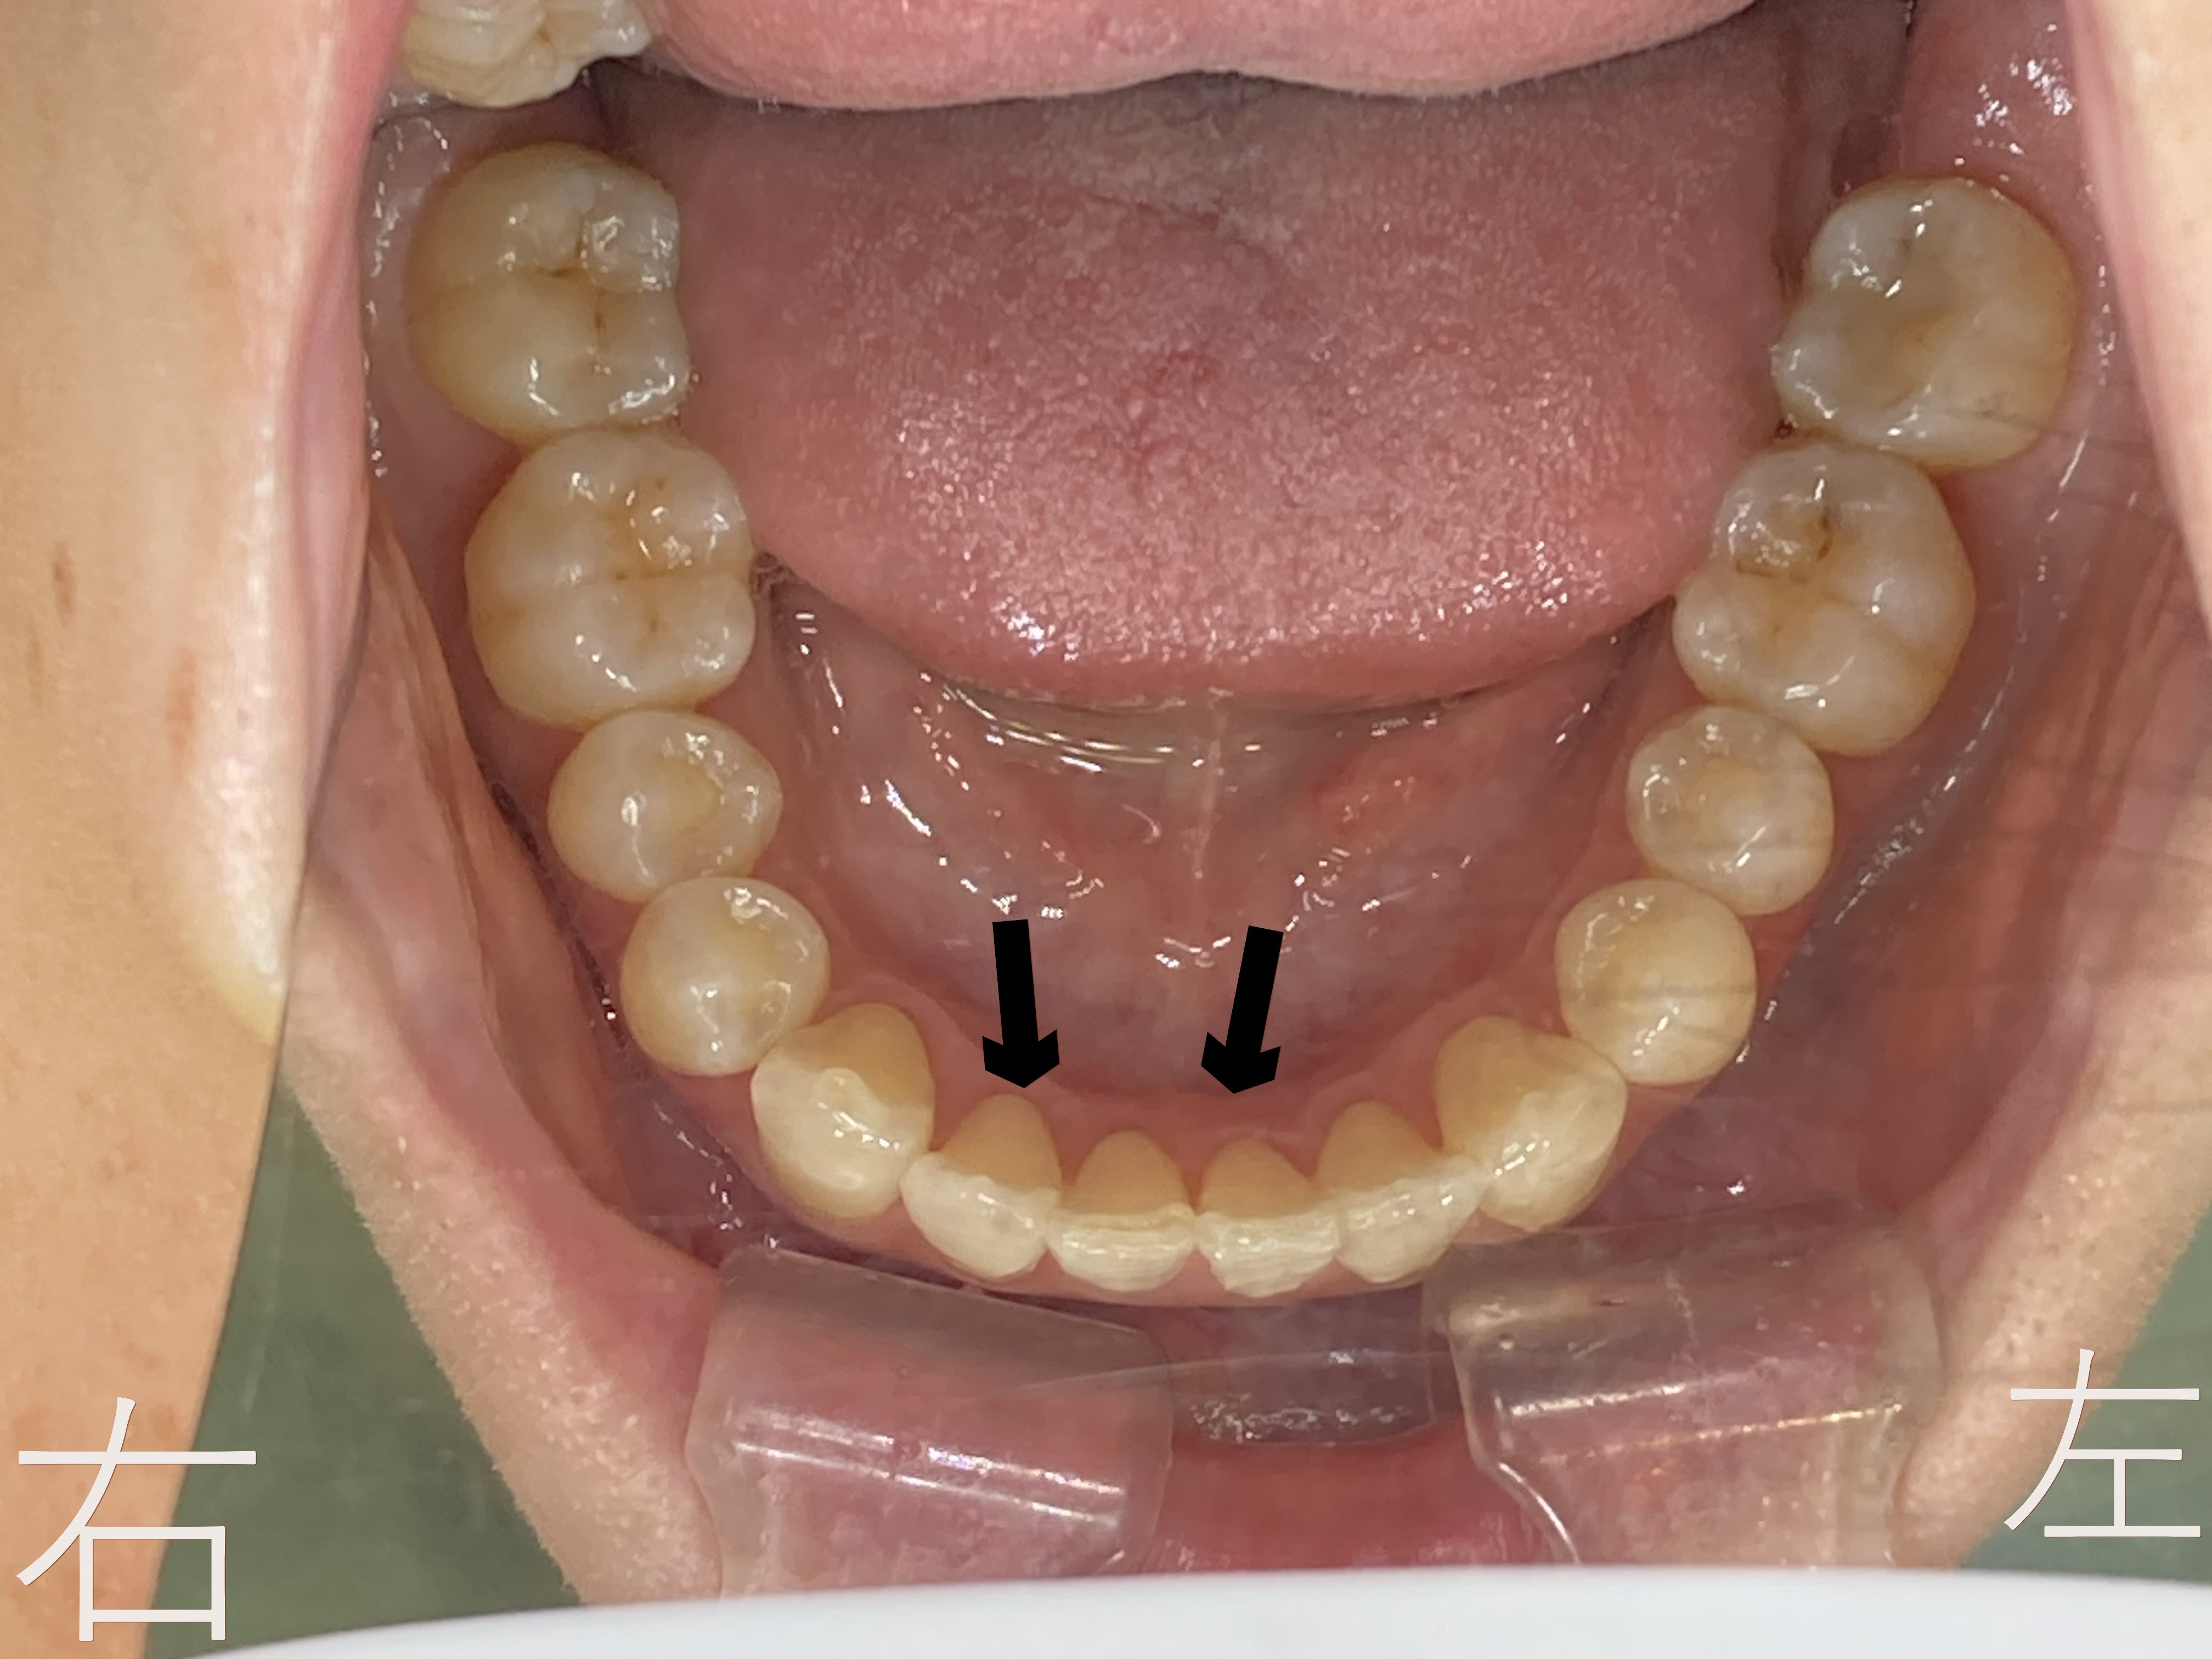

上記はボタン(マルチブラケット)を外した後の下顎左右前歯部(黒色矢印)の口腔内写真です。

下顎前歯部のゆがみ【叢生】が解消していることが確認できます。